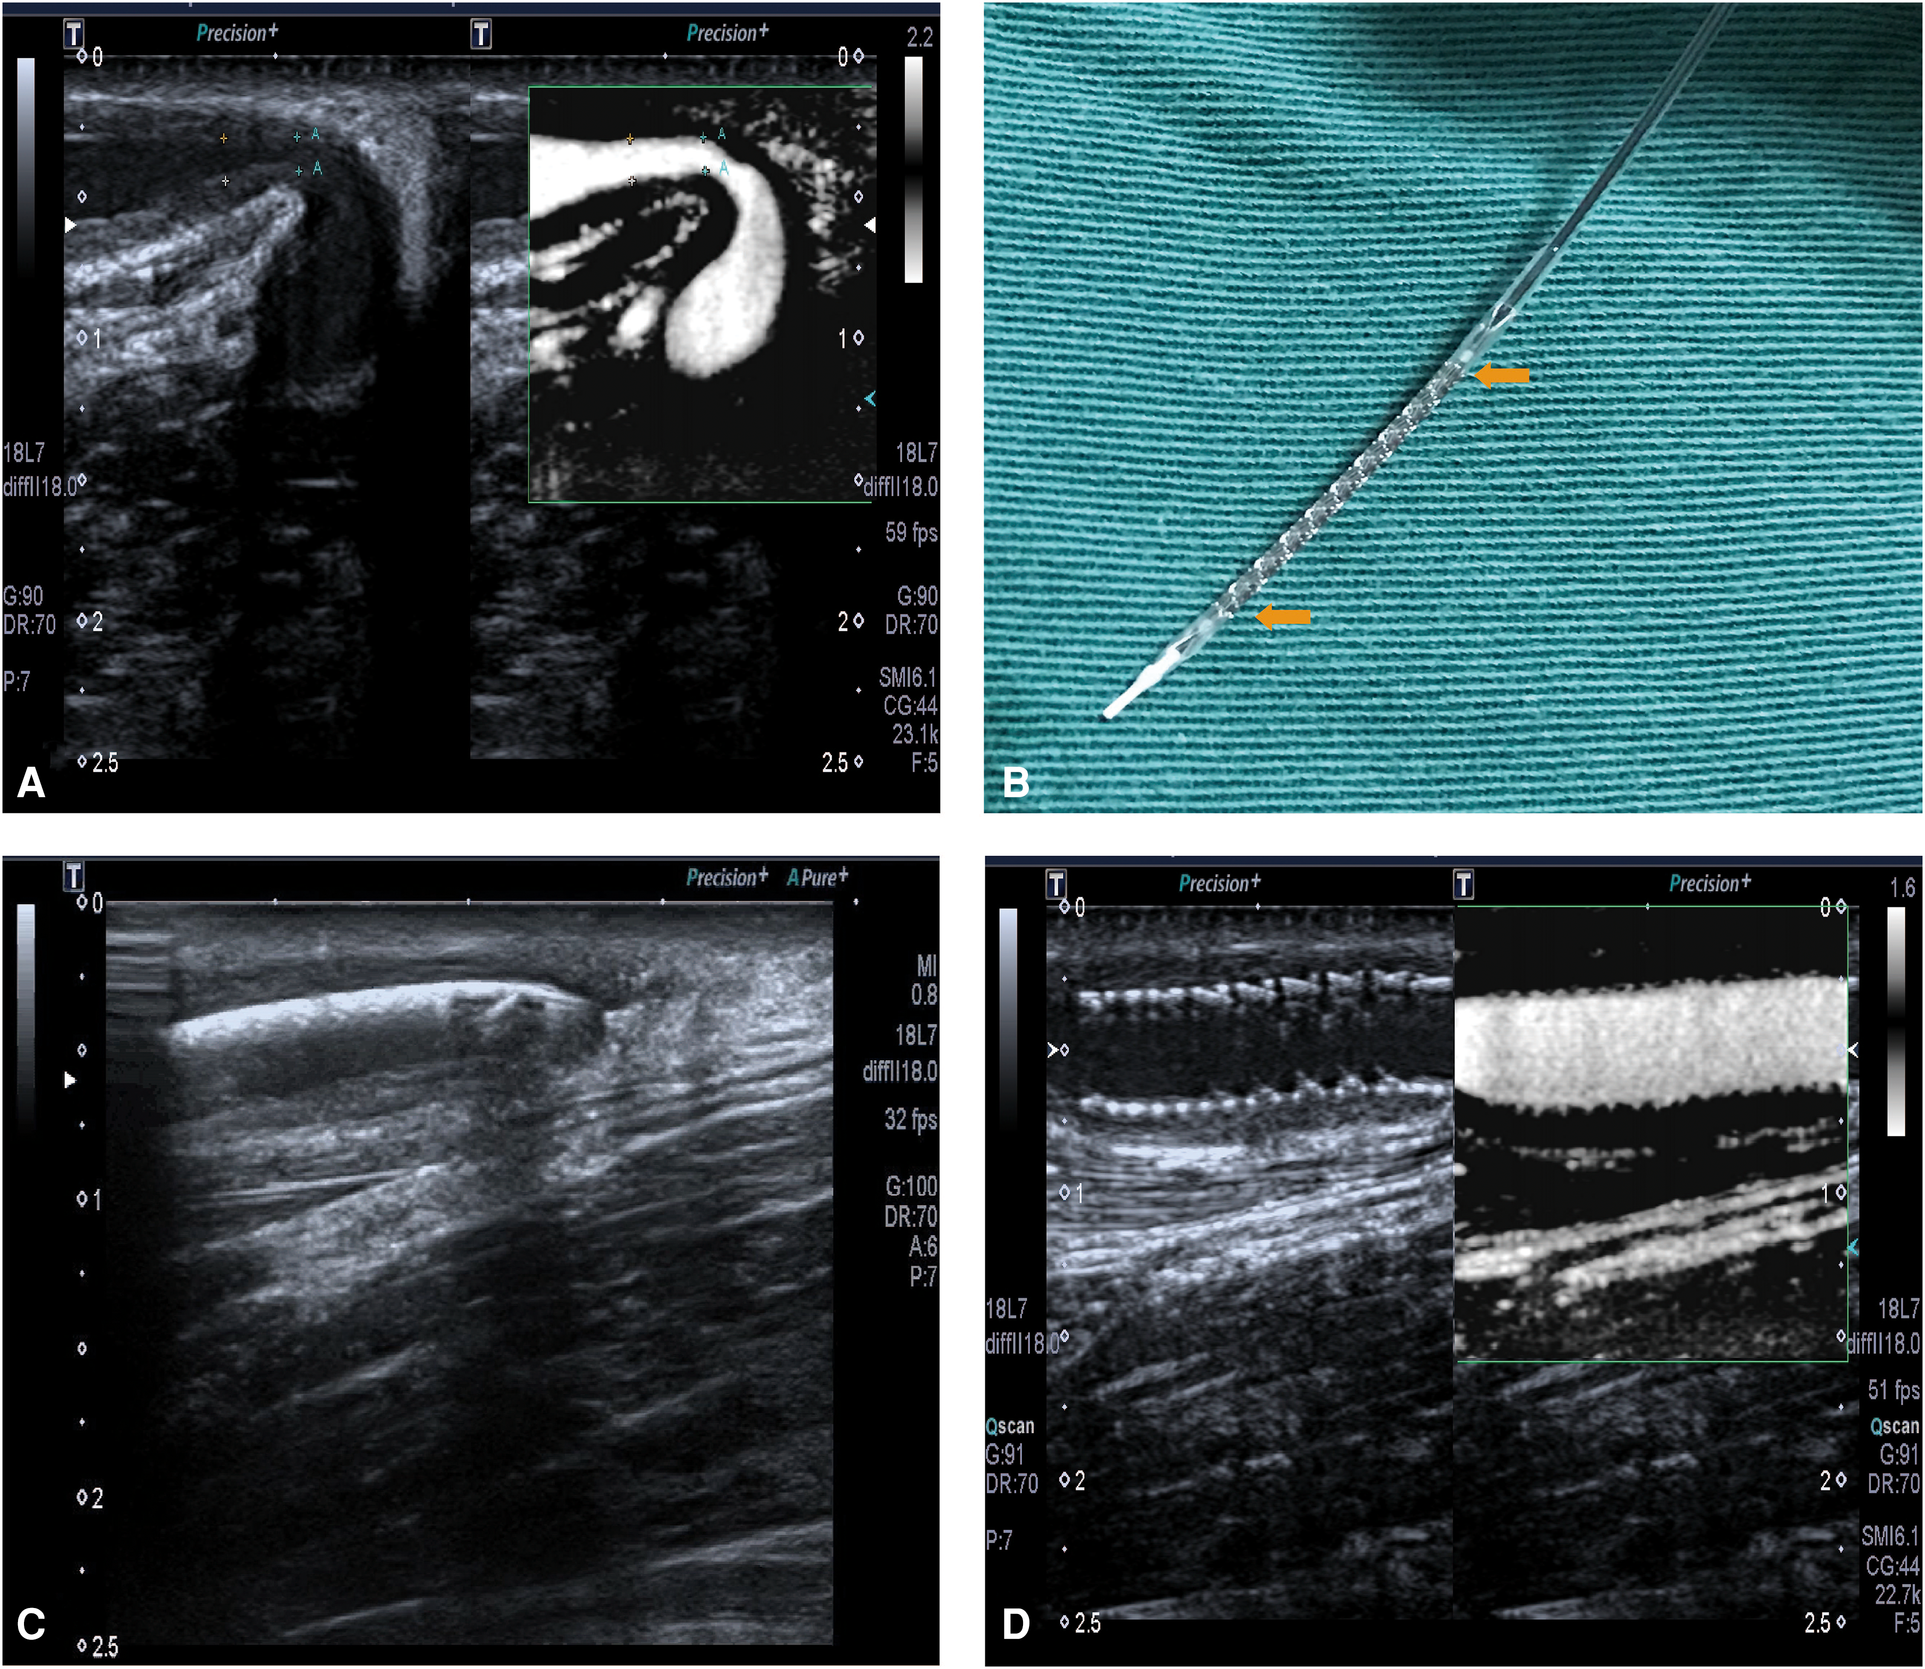

On 23 May 2017, this patient was hospitalized again because of decreased flow volume in the right forearm AVF. Preoperative ultrasonoscopy indicated a significant juxta anastomotic stenosis, with a diameter of 1.0 mm and a length of 1.5 cm (Figure 1A). No thrombosis or calcification was found. Because of the short duration of patency maintenance after each repeated PTA, after a discussion, the team decided to perform another PTA with RES placement in the right forearm AVF. Informed consent was obtained before the procedure.

Figure 1

(A) The restenosis of right forearm autologous AVF on 23 May 2017. (B) RES. The yellow arrows show the main body of the stent, with a balloon inside it. (C) The ultrasound localization of RES which shows the RES was placed at the site of stenotic lesion. (D) The fully expanded RES, with a patent blood flow.

After the brachial plexus block, a 5F-R vascular sheath (Terumo, Tokyo, Japan) was inserted into the cephalic vein. A guide wire (Abbott Vascular, Santa Clara, California, USA) of 0.014 in. was advanced along the vein slightly across the stenotic lesion. A balloon of 5 mm × 20 mm was advanced along the guide wire and across the stenotic lesion to the anastomotic site, followed by balloon angioplasty of the stenotic lesion, the outflow vein, and the anastomotic site using 20–24 atm, repeated three times. The balloon was subsequently removed. Then the RES (NOYA, Beijing, China), a balloon-expandable stent with a diameter of 4.5 mm and length of 22 mm, was placed in the stenotic lesion with the guidance of ultrasonography (Figures 1B,C). The RES was fully expanded by a balloon angioplasty using 16 atm.

After PTA and RES placement, the ultrasound images showed that the diameter of the brachial artery was 5.9 mm, with a flow volume of 521 ml/min. In the segment of the cephalic vein near an anastomosis, a 22 cm stent was observed. The stent was closely fitted to the vascular wall, and a color Doppler ultrasound showed filled blood flow through the stent, with a peak velocity of 210 cm/s (Figure 1D). The diameter of the middle segment of the forearm cephalic vein was 3.8 mm, with an intimal medial thickness of 1.4 mm and a peak velocity of 256 cm/s.